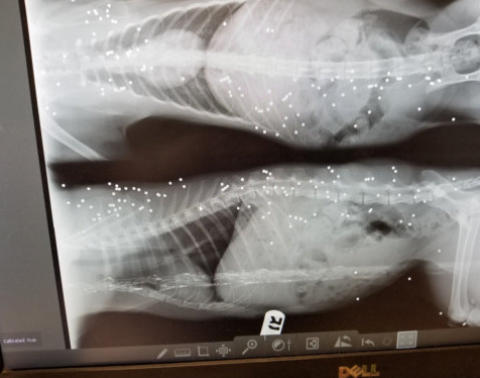

His x-rays show the life of hell he had endured

Blind Gender: Male Approximate age: Arrived From: North Carolina Arrival Day: August 2018 Uncle Fester spent his life trying to stay out of the way of people who might do him harm, cars, and other dangers of life for a blind cat. This was his story, until he came to BCR in 2018. By the time a good Samaritan had alerted someone about this poor cat who had been looking for food, he’d been through so much. When he got to BCR, he had many wounds and a broken leg that had healed incorrectly. It’s most likely that Uncle Fester lost his sight due to an untreated upper respiratory infection. When we took Fester to the vet for his first thorough medical exam, his X-ray revealed that he had been shot at close range with bird-shot. Those pellets are still visible under his skin. Although they aren’t painful, they are there as a reminder of his past. However, Uncle Fester’s story has a very happy ending! This kind and gentle cat today lives a safe, healthy life full of love and attention. Despite his horrible life on the street and the abuse he suffered, he is now in a place where he will never be abused, afraid or hungry again. He is – in spite of all he’s endured - a very loving cat who still loves and trusts people. Uncle Fester is also a great friend to his fellow BCR cats, always trying to make new arrivals to his room feel safe. All of them like to cuddle with him! You may catch Uncle Fester in a cuddle puddle on our live 24-hour cameras in House 2, Room 2. Live Pet Camera HERE

The horrible things humans think is ok to do to an innocent animal. That is bird shot, I would guess from a very close range. We were horrified when we saw the x-ray!